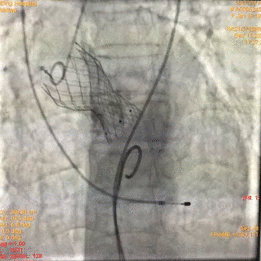

术中影像

图片

根部造影

球囊预扩

瓣膜释放

瓣膜释放完毕

手术结果

术后造影及超声探查未见瓣周漏,跨瓣压差术前56mmHg,术后几乎无压差,术中及术后未出现相关并发症,手术圆满完成。